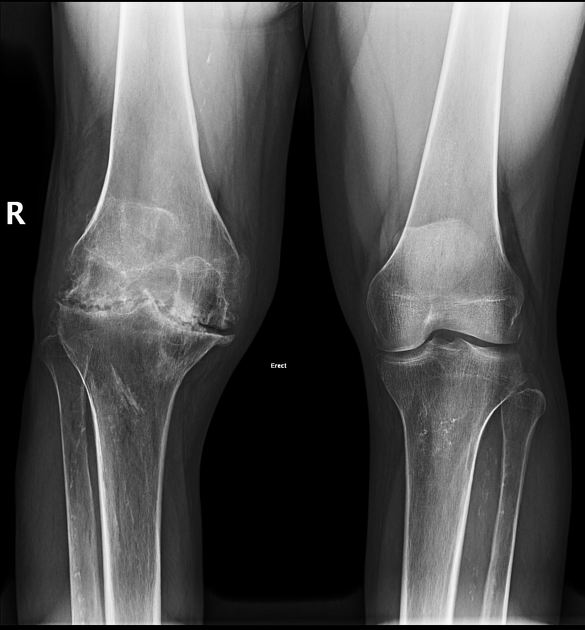

만성 혈우병성 관절병증으로 인한 통증은 상태에 따라서 발생될 수도 있으며 뼈에는 가골이 형성이 될 수 있으며 뼈의 밀도가 감소하여 골다공증이 발생합니다. 그리고 연골 간 공간이 매우 좁아지게 되며 관절면이 불규칙해집니다. 그러면서 관절의 변형이 나타날 수 있습니다.

또한 반복적인 출혈 정도에 따라서 만성 혈우병성 관절병증(chronic hemophilic arthropathy)으로 될 수 있습니다. 이 질환은 만성활액막염과 함께 혈관절증이 진행이 되어 관절 연골에 손상을 받게 된 상태로 출혈 정도에 따라서 10대 이하에서도 발생될 수 있습니다. 이 질환이 만성화되면서 활액막과 관절주머니는 점차적으로 섬유화(fibrosis)가 되고 부종은 줄어들게 됩니다. 또한 관절이 섬유화 됨에 따라서 굽힘 구축과 운동성의 감소로 인한 기능 상실을 가져오게 됩니다.